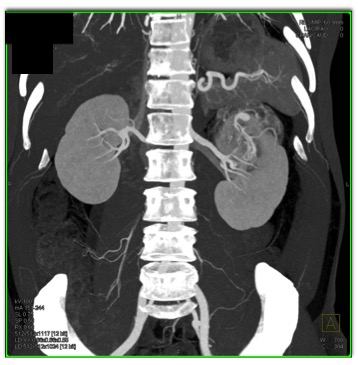

The best diagnosis in this case is?

lipid poor AML

MEST tumor (Mixed Epithelial Stromal Tumor)

clear cell renal cell carcinoma

papillary renal cell carcinoma